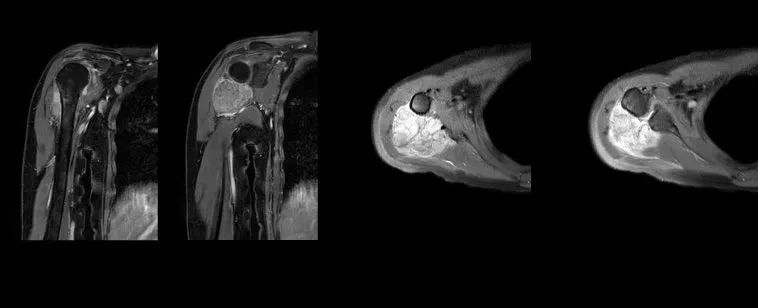

Aunt Liu, 56 years old this year, had right shoulder pain several years ago. It has significantly worsened over the past 4 months, especially at night. The local hospital found “right humeral cortical side tumor lesions” on the film. She came to the Orthopedics and Tumor Department of Wuhan Union Hospital for treatment. After Professor Liu Jianxiang’s team received the patient, shoulder joint CT and MR examinations were performed, and the tumor involved the proximal humerus and scapula, with a wide range. First, local puncture biopsy was performed for the patient, and the pathological diagnosis was confirmed as “biphasic synovial sarcoma of the right shoulder”. Considering that the tumor is a malignant tumor and the patient currently has a single focus in the whole body, the team formulated an individualized treatment plan for the patient-complete removal of the proximal end of the humerus and half of the scapula, and 3D-printed artificial reverse shoulder joint replacement. The aim is to achieve tumor resection and prosthesis reconstruction, thereby restoring the patient’s normal shoulder joint structure and function.

Postoperatively, the patient’s condition was good, and they were able to move with the aid of a brace on the affected limb on the second day and perform passive shoulder joint movements. Follow-up X-rays showed good positioning of the shoulder joint prosthesis and good functional recovery.